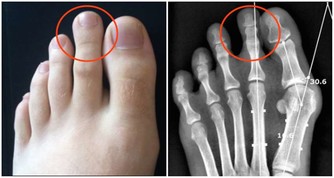

4、小腿圍

法國一項研究發現,小腿圍小於33公分的女性,患有頸動脈斑塊的風險相對更高,而這是中風的一個已知風險因素。小腿肚上的皮下脂肪會提升並儲存能夠促進血液循環的脂肪酸,以避免頸動脈斑塊形成。

【達標值】大於33公分

【測量方法】

用皮尺水平圍繞小腿最豐滿處進行測量。